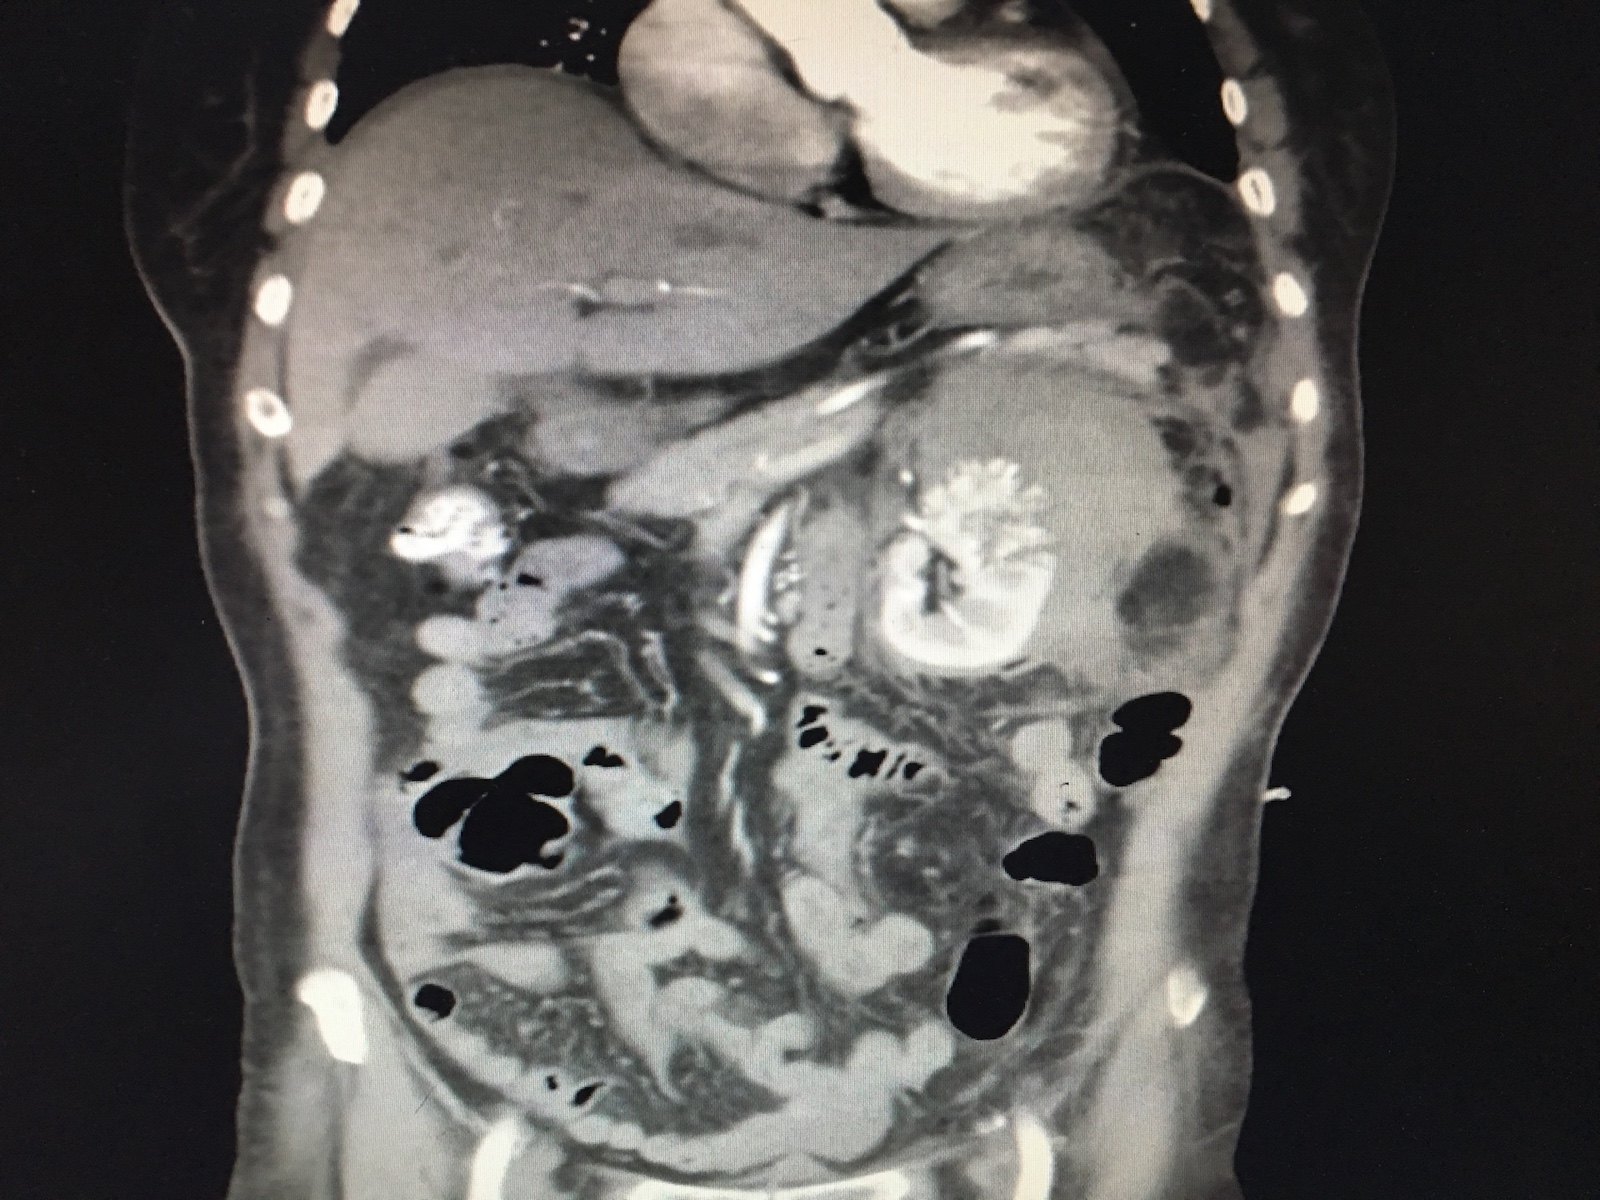

腹痛伴头晕3小时,巨大肾错构瘤破裂一例